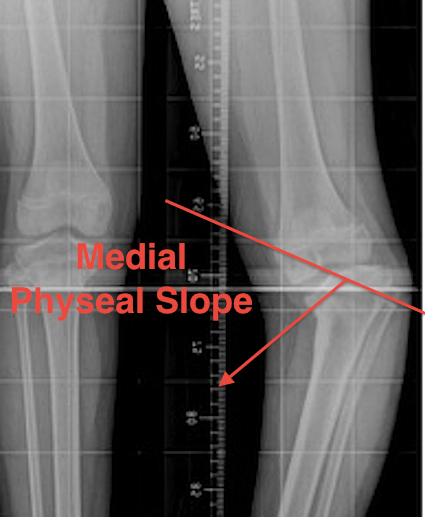

Medial Physeal Slope

Technique

- line through medial physis & line through lateral physis

Measurements

- significant if > 60°

- prognostic of progression